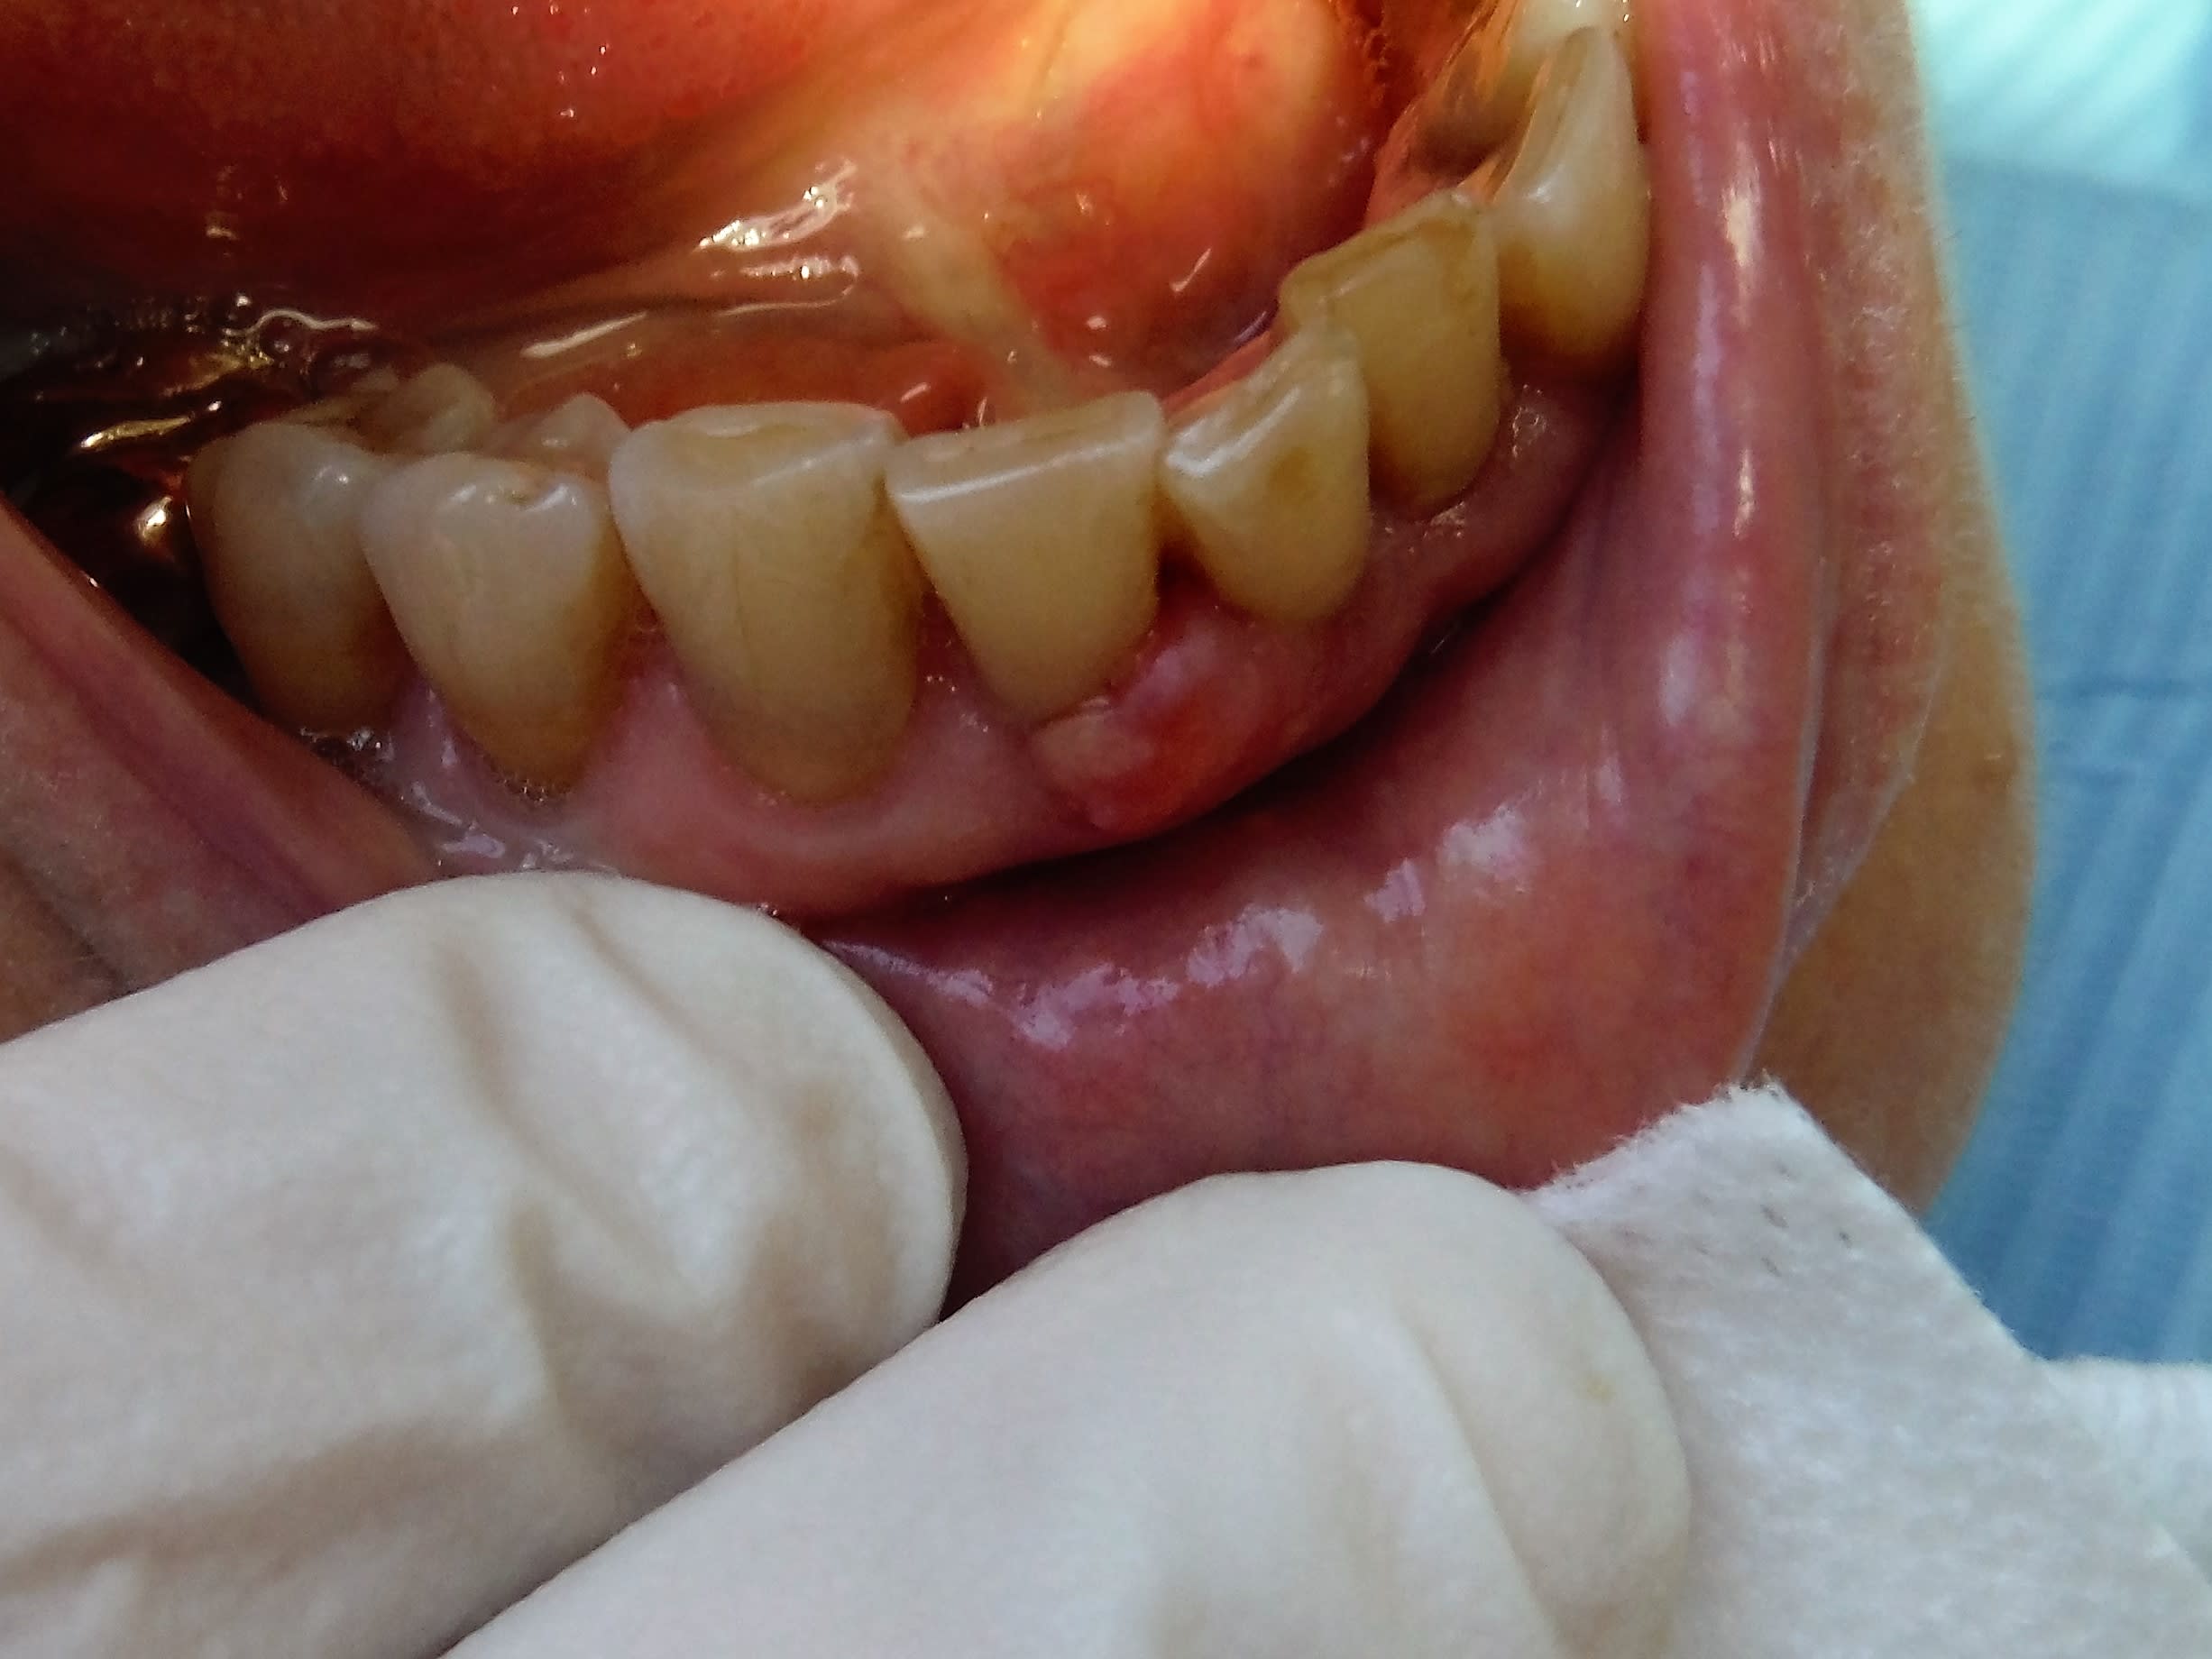

Là c'est autre chose... carcinome épidermoïde. Il n'y a pas que les dents en bouche.

Suis pas certain et échaudé, biopsie.

Paro ras, os ras dents ras. Douloureux, "dur" et peu hémorragique, non sessile, pas trop mobile.